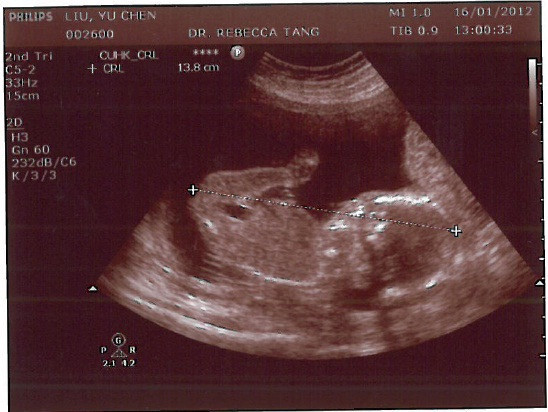

◆【20W2D】結構性超聲波

輪到我檢查時,不愧是私 家 醫師又有陸客客人,醫生態度溫和友善,詳細的檢查招財的每一個器官,也同步用普通話跟我說明目前看到的怪東西是哪個部位,如心臟、脊椎等等,老實說,之前懷招弟時,美國醫生說的我都聽不懂,現在聽到招財的介紹,真是如夢初醒一般啊!

醫生也很大方的印了7張超音波照給我,還有一張檢查期間的DVD光碟,雖然說羊毛出在羊身上,但回家後還可以看到招財在動的紀錄,真是很有趣啊!今天也確定了招財是女生,老實說,我聽到時有點想哭,不過後來經過鍵哥的開導,我們能順利有小貝比,而且小貝比又是健康的,那才是最重要的。

招財的側面, 醫生到底在量些什麼呢?

即使要成為兩個孩子的媽的我, 還是不知道這在照哪裡?

"理論上"是頭吧? 還是心臟? 啊~~我不知道啦!!

在看招財的鼻梁~~

很確定的是個女孩兒~~~